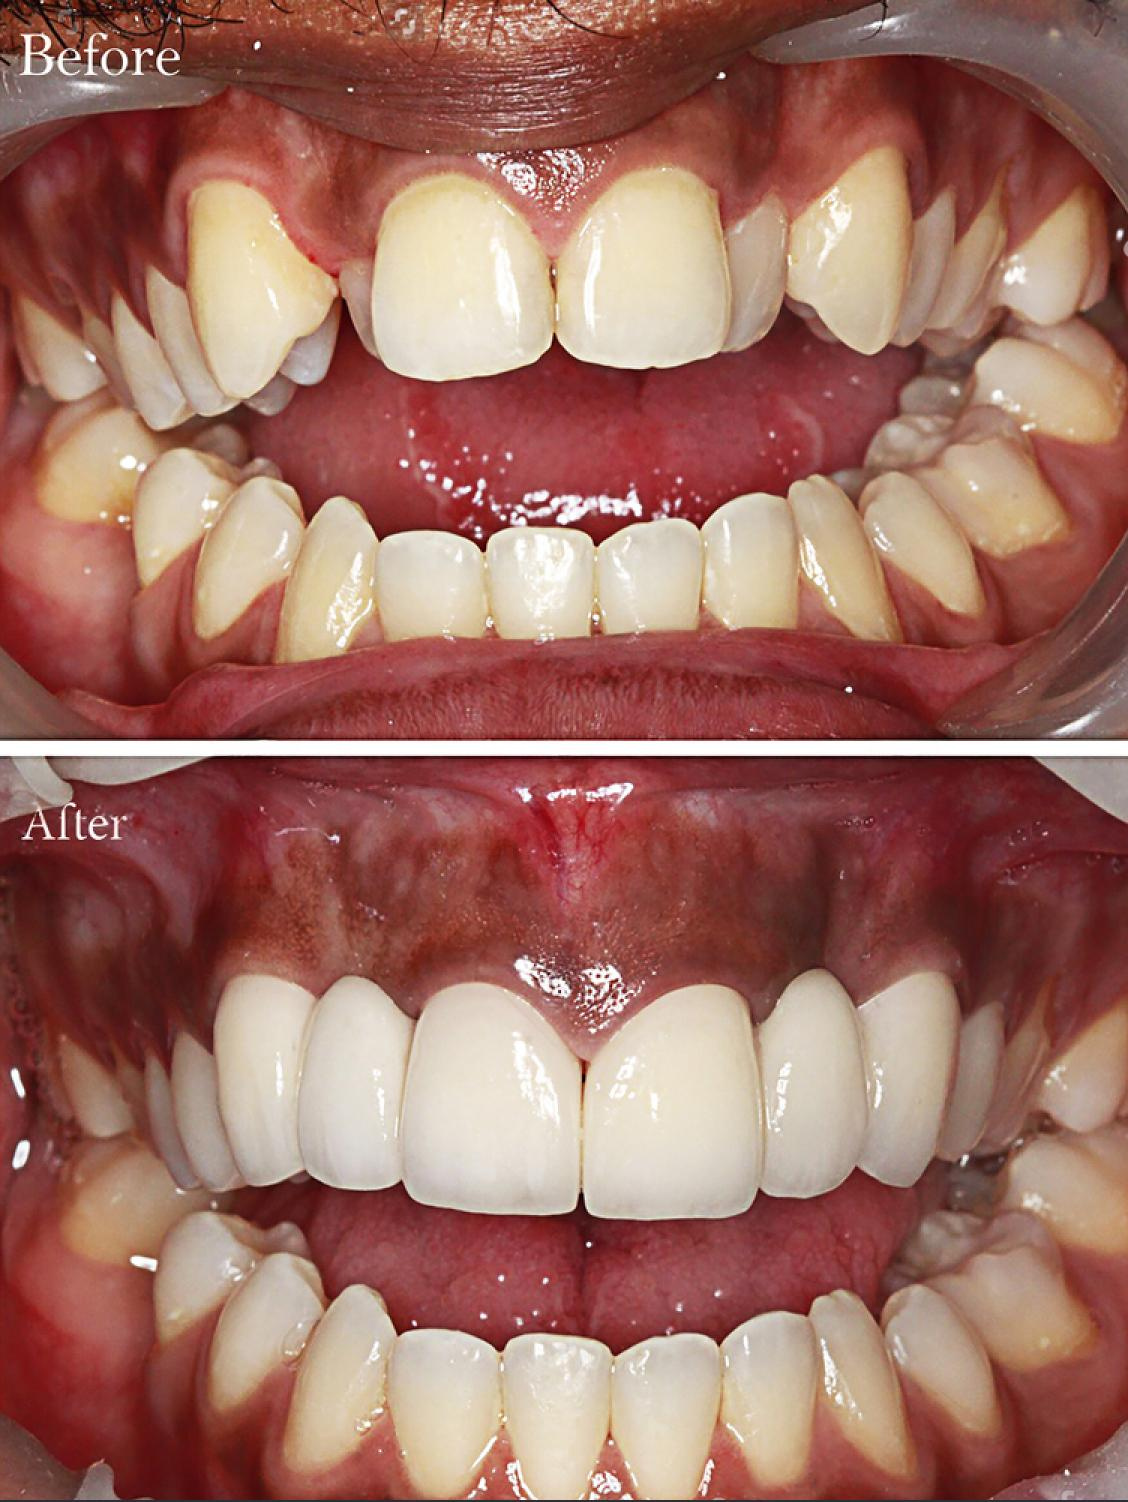

Real Results. Real Confidence.

At Al Rayashi Dental Center, we believe that every smile tells a story — and we’re proud to be part of so many incredible journeys. Our Smile Transformations page showcases real patients who have trusted us to restore their confidence and enhance their dental health.

From subtle refinements to dramatic changes, these before-and-after cases highlight the power of expert care and advanced dental technology.

Smile Transformations